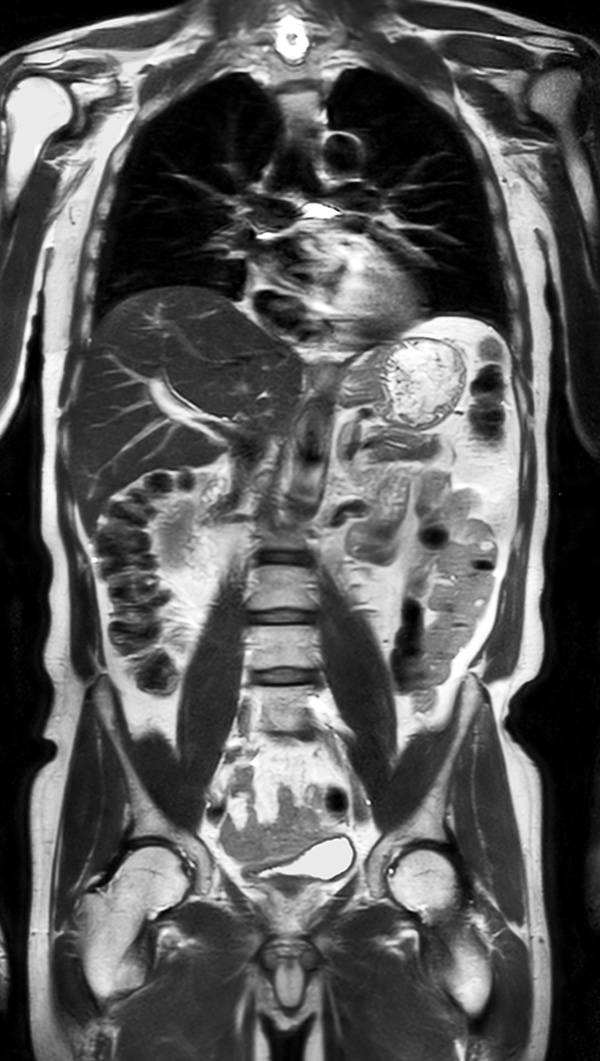

Coronal T2w TSE (MobiView)